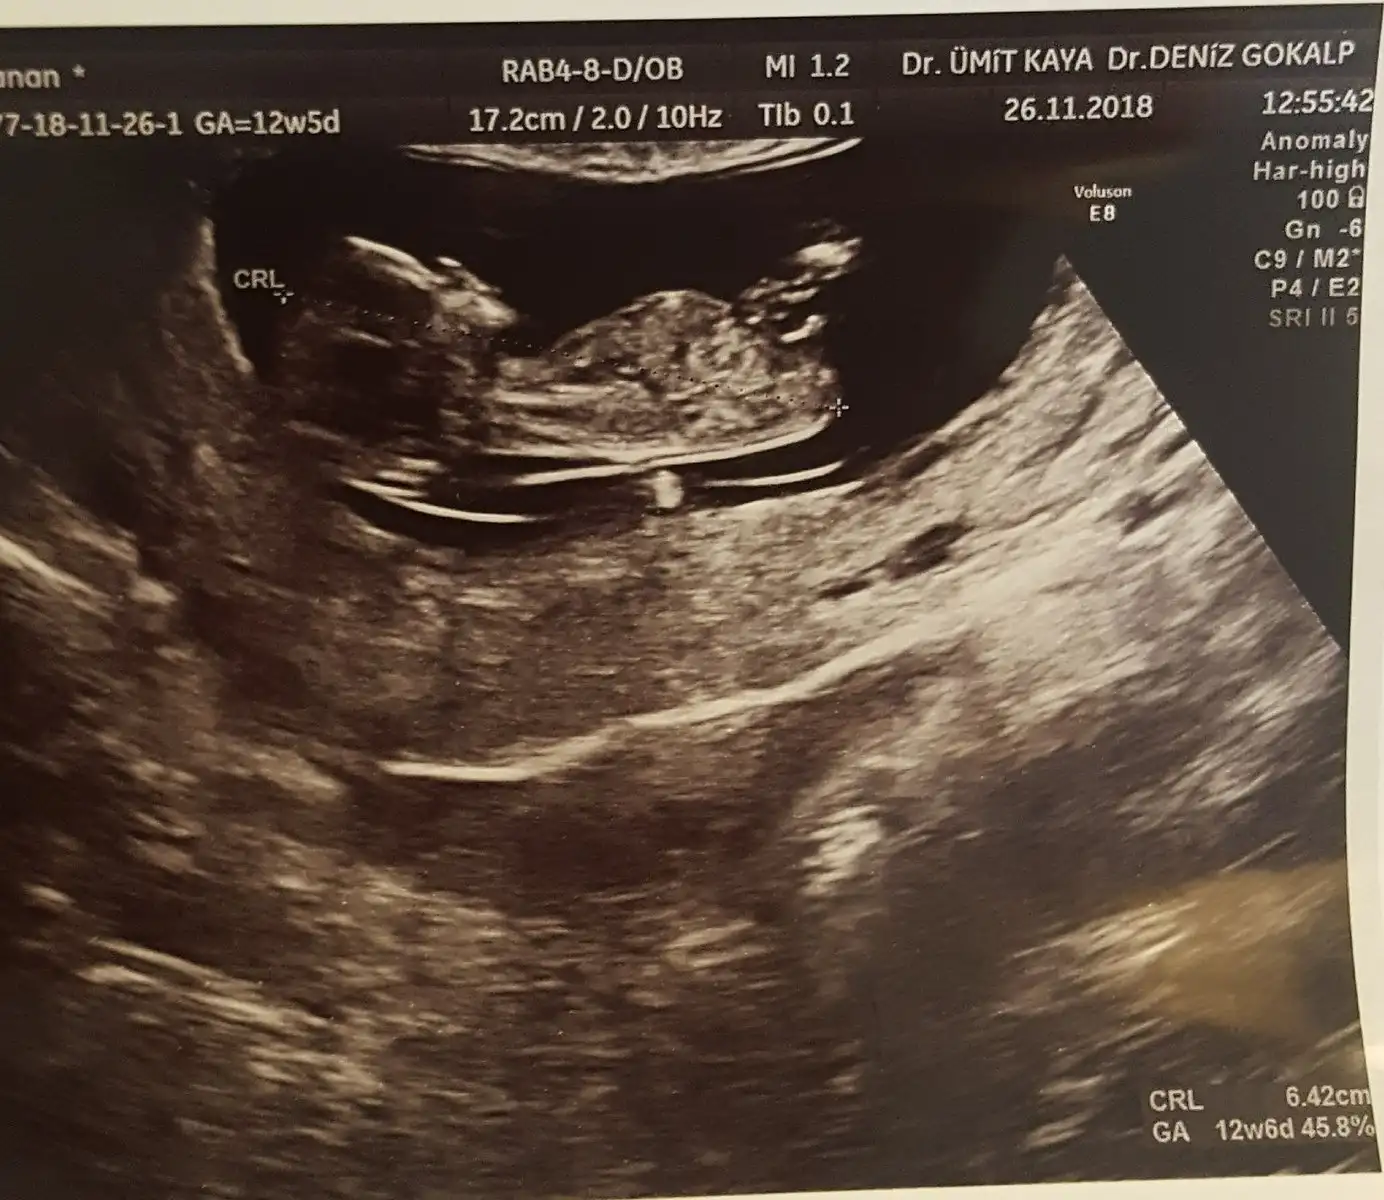

Resim yükledim kızlar ama ben bu usg Fotoğraflarından hiç bişi anlamıyorum başını poposunu bile ayıramıyorum ki nerde cinsiyet tahmini anlayanlardan yorum bekliyorum

İlk doktor 11+4 te açı bulamamış kızı andırıyor demişti. Bugün başka doktora gittim 12+5 ti erkek dedi çıkıntı var ama erken daha dedi bilmiyorum yani farklı dediler